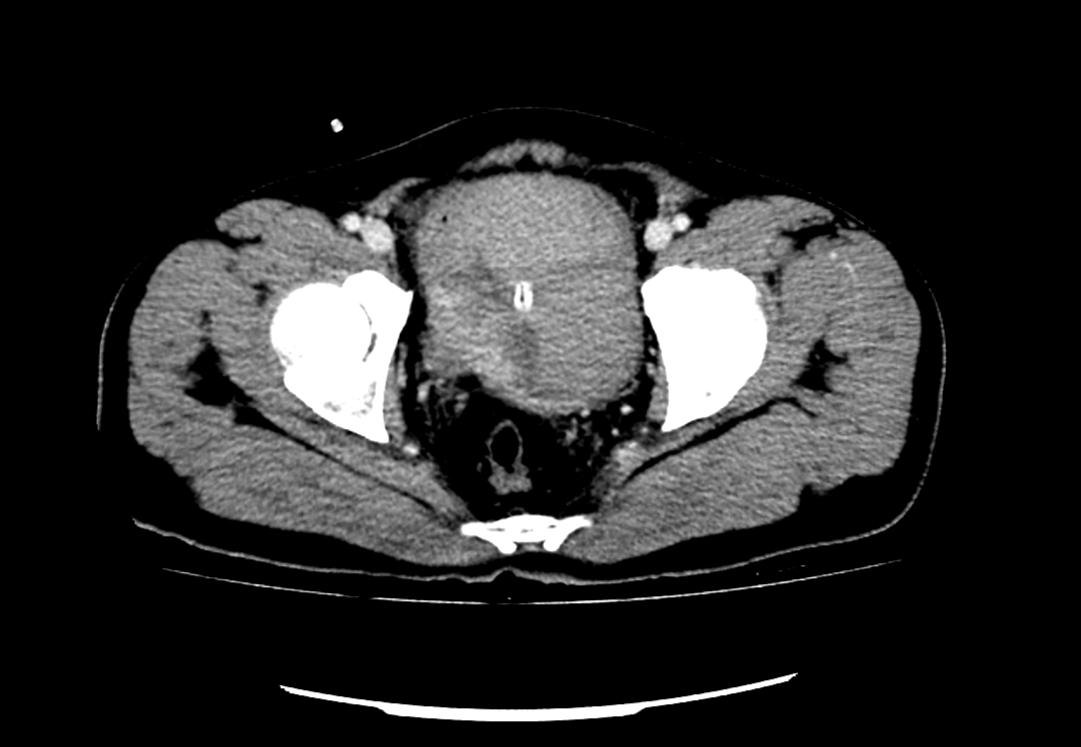

患者為53歲的男性,患者因肉眼血尿就診我院門診,行泌尿系CT考慮膀胱占位,建議患者住院治療,入院后完善膀胱MRI檢查進(jìn)一步診斷膀胱腫瘤,侵犯肌層。行膀胱腫物激光切除后,病理學(xué)檢查明確“膀胱高級別尿路上皮癌,肌層浸潤”診斷,結(jié)合泌尿外科診療指南建議行根治性膀胱全切術(shù)。

泌尿外科醫(yī)生團(tuán)隊(duì)術(shù)前將患者情況上報(bào)醫(yī)務(wù)科,并組織了多次會(huì)診?;颊?/span>“肌層浸潤性膀胱癌”診斷明確,術(shù)前完善心肺功能排除無明顯手術(shù)禁忌,結(jié)合指南推薦及泌尿外科團(tuán)隊(duì)成員綜合意見,決定在全麻下行腹腔鏡下膀胱根治性切除+盆腔淋巴節(jié)清掃+回腸代膀胱手術(shù)。術(shù)前嚴(yán)格完善準(zhǔn)備工作,手術(shù)歷經(jīng)7小時(shí),完整切除了患者的膀胱、前列腺及精囊,并行回腸代膀胱。手術(shù)順利,術(shù)后3天可正常行走,復(fù)查患者各項(xiàng)指標(biāo)正常。